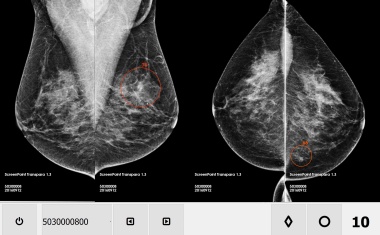

Eine neue Software unterstützt Mediziner dabei Brustkrebs bereits im frühen Stadium zu entdecken. Die KI-basierte Mammographie steht allen Patientinnen zur Verfügung und erhöht ihre Überlebenschance.